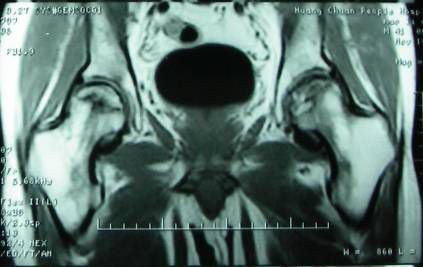

骨闪烁成像显示热区中的冷区,组织活检证实骨坏死,骨闪烁显像显示热区或冷区损害,MRI显示股骨头内低信号点见(图2)。

(图2)MRI 显示股骨头内低信号点双侧股骨头坏死